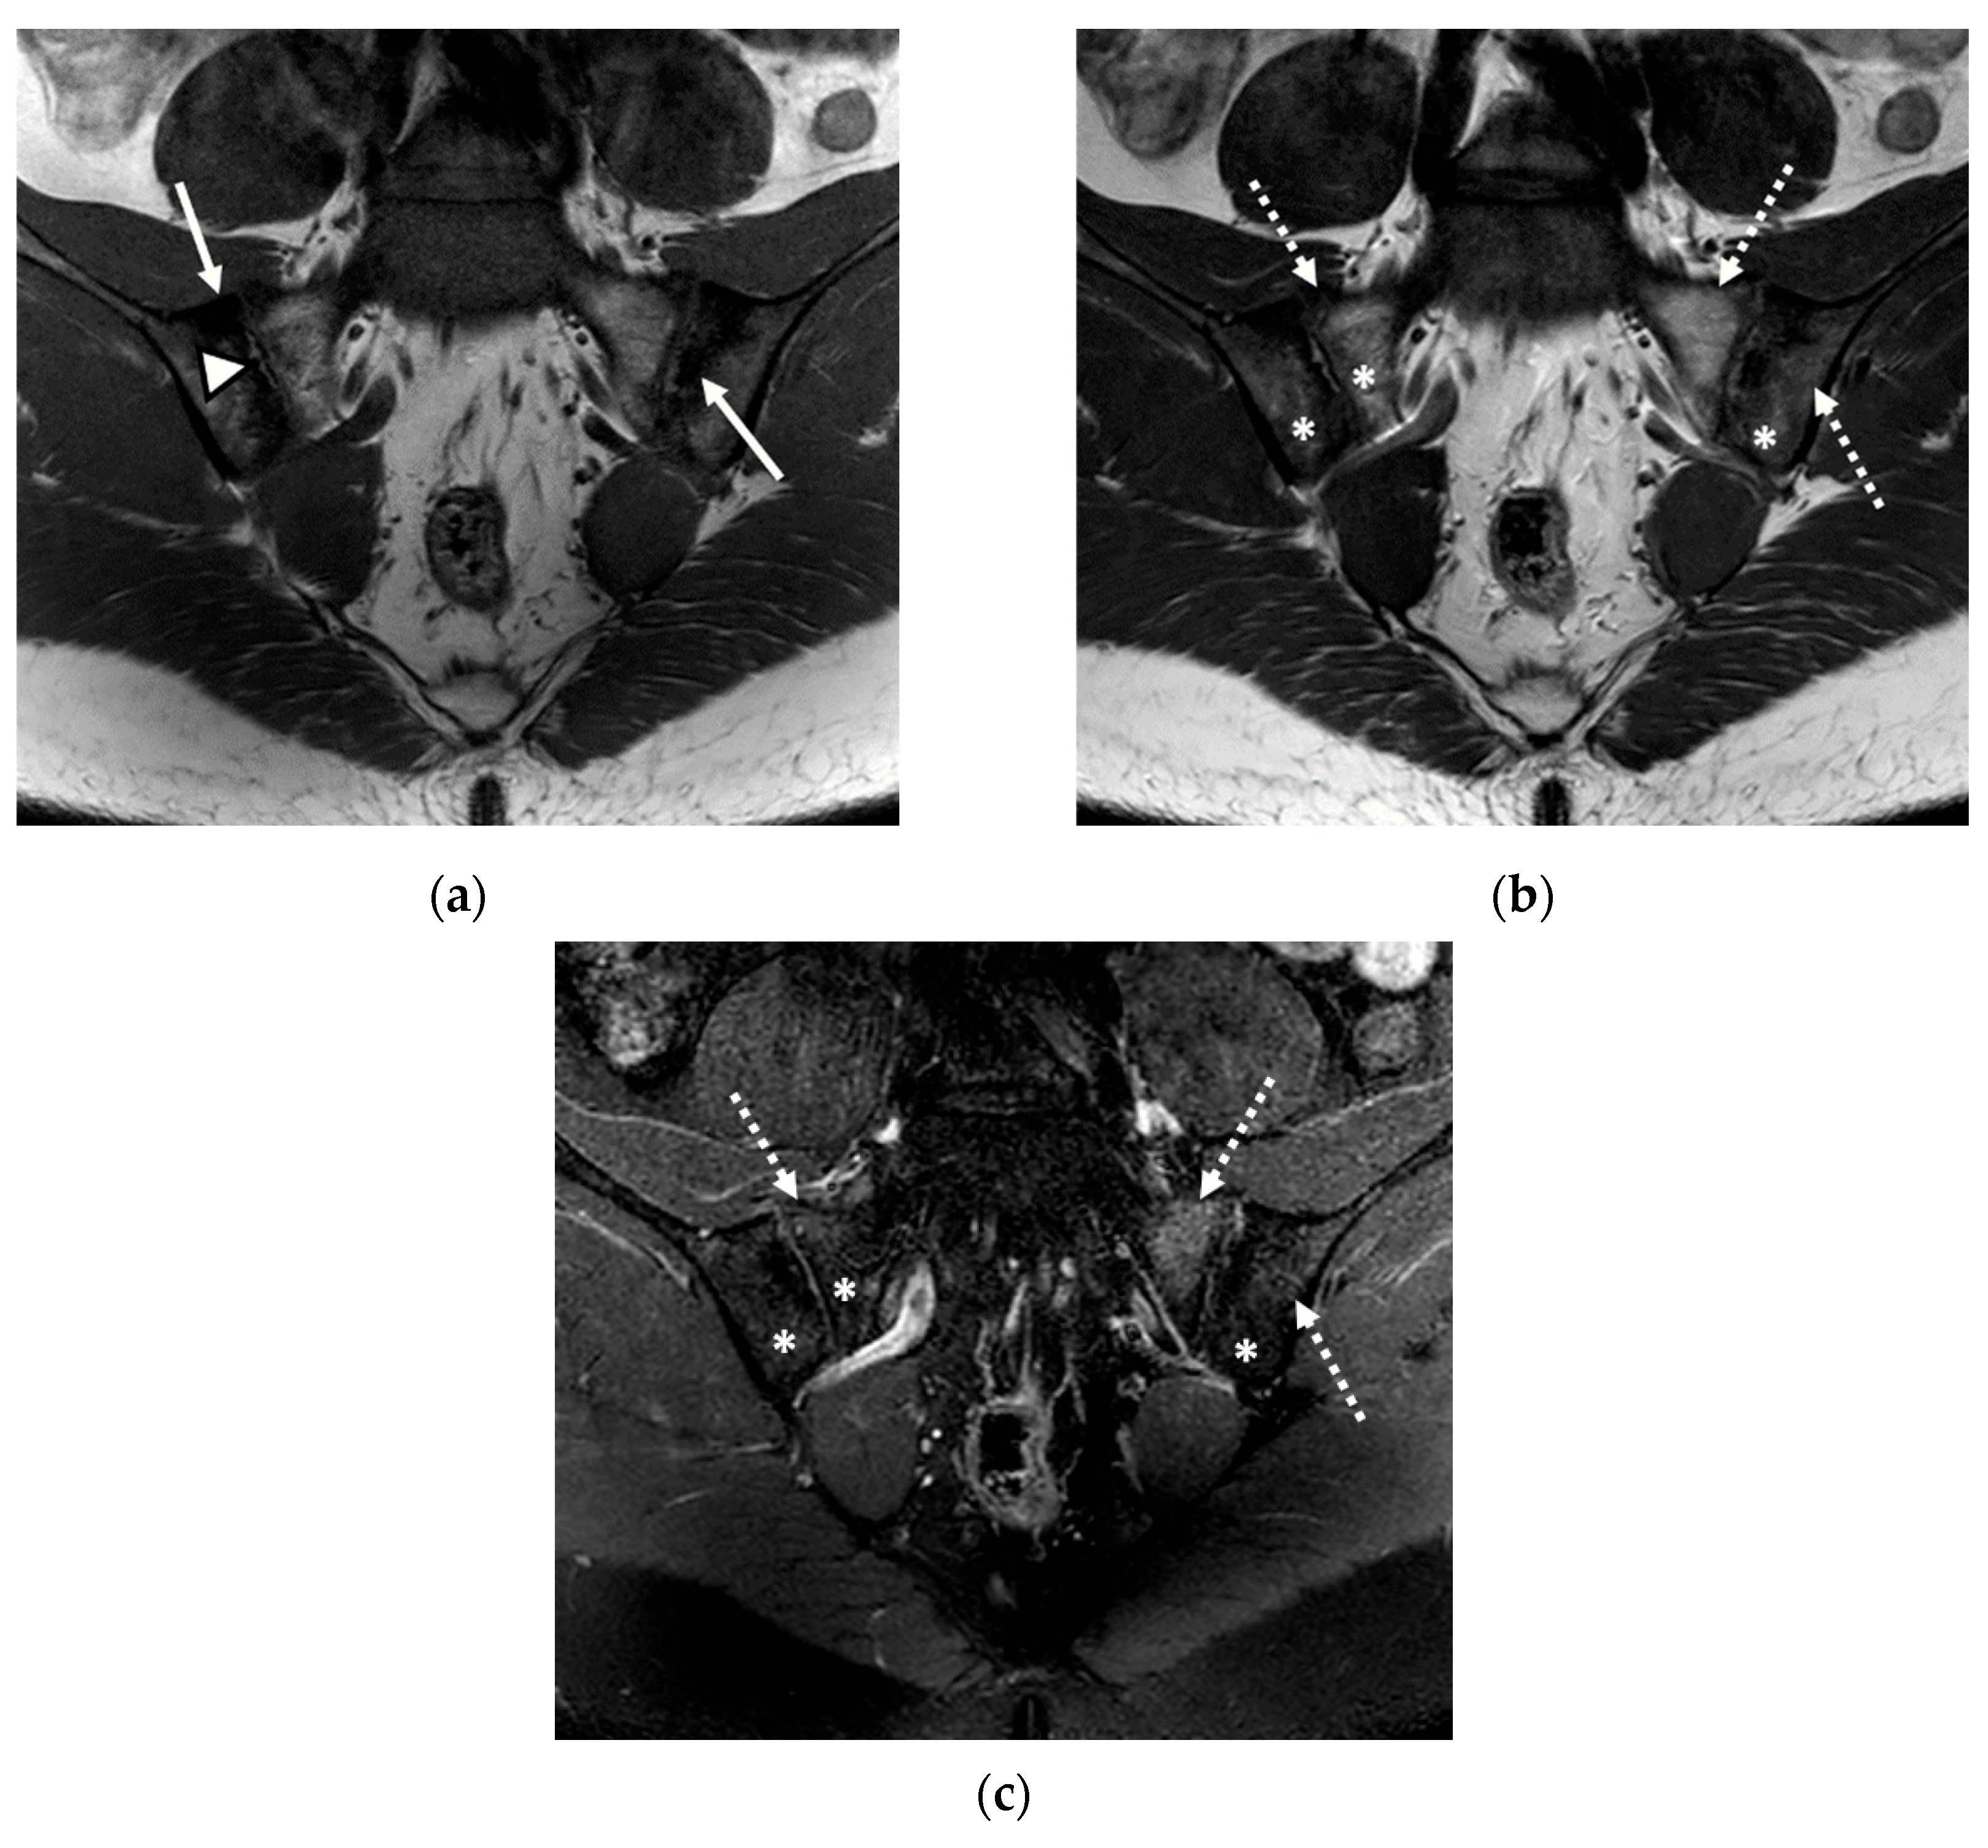

Figure 3.

The MRI aspect of the sacroiliac joints included pseudo-widening of both sacroiliac joints, with marked bone marrow edema (star) of both the sacrum and the right iliac bone, in the proximity of the ipsilateral sacroiliac joint space, right iliac bone erosions (discontinuous arrow), bilateral subchondral sclerosis (continuous arrow), and fat metaplasia (asterisk), affecting the left iliac bone, and the left part of the sacrum and backfill (arrowhead) of the left sacroiliac joint space: (a) T1-weighted sequence; (b) T2-weighted sequence (without fat suppression); (c) STIR sequence.